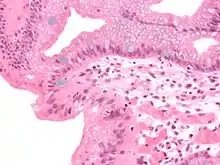

Micrograph of a gastro-esophageal junction with pancreatic acinar metaplasia. The esophageal mucosa (stratified squamous epithelium) is seen on the right. The gastric mucosa (simple columnar epithelium) is seen on the left. The metaplastic epithelium is at the junction (center of image) and has an intensely eosinophilic (bright pink) cytoplasm. H&E stain. |